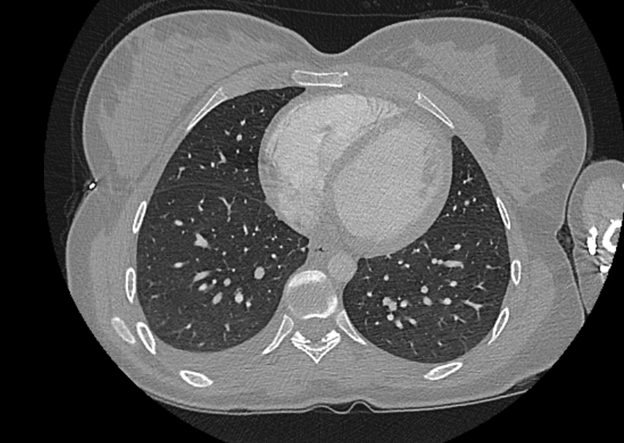

Cases of the Week

Check out our Cases of the Week!